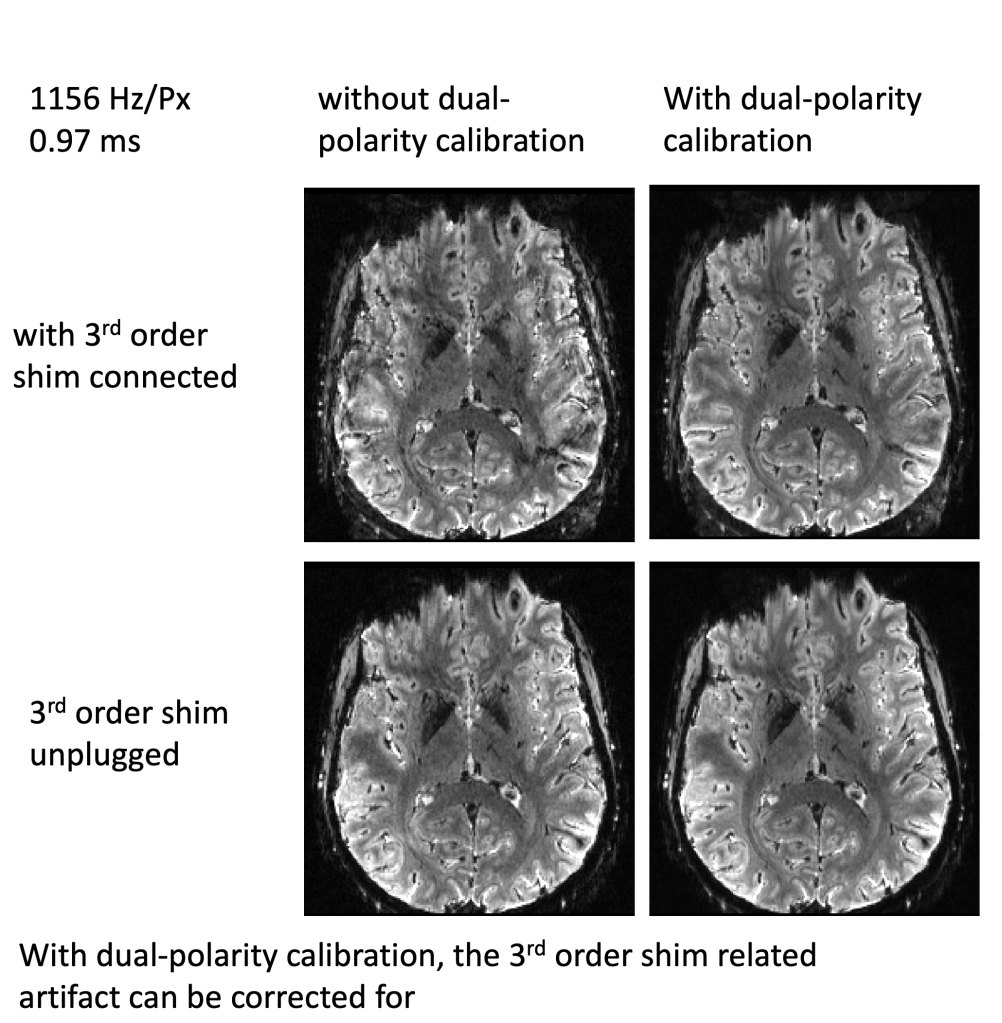

Alternatively, it’s also possible to calibrate for the respective gradient trajectory imperfections in the reconstruction pipeline by means of a dual polarity readout.

I looked at phantom data (four sessions) and human data (four sessions). Each acquisition was performed twice, with the 3rd order shim plugged in and with the 3rd order shim unplugged. I tested the SIEMENS product sequence TURBOFLASH, the CMRR-multiband 2D-EPI sequence, and the DZNE 3D-EPI sequence. Images are acquired across a spectrum of echo spacings. The complete protocol PDFs are available on Github. Experiments were performed on the 7T Terra with SC72, with the following forbidden frequencies: 339.5-394.4 Hz and 500-600 Hz and 950-1250 Hz, corresponding to bi-polar EPI echo spacings 0.41-0.52 ms and 0.83-0.99 ms and 1.27-1.47 ms.